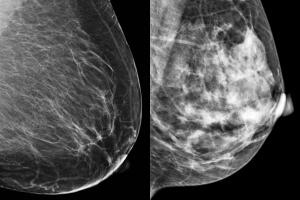

En estas pruebas, el tejido mamario denso se ve blanco, el mismo color que tumores o masas en los senos, lo que hace que sean menos precisas en mujeres con alta densidad.